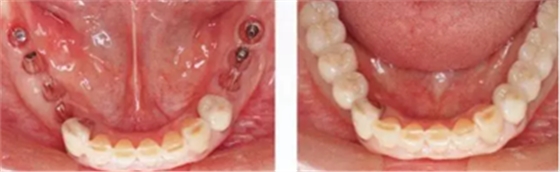

▲圖10-9,10

頰舌側都獲得了充足的角化齦,菌斑控制狀態(tài)良好。

▲圖10-7,8

圖10-7 術前。

圖10-8 術后。種植體周圍獲得了充足的角化齦。

▲圖10-11,12

佩戴最終修復體后2年的狀態(tài)。頰舌側角化齦寬度均充足。